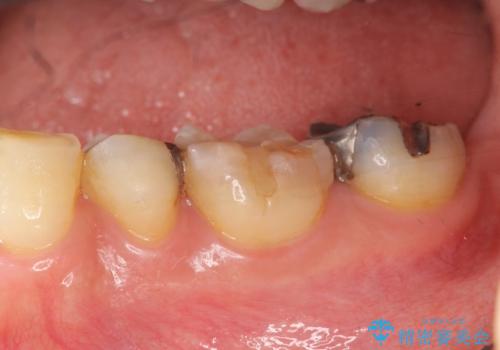

銀歯の下で虫歯の再発 拡大鏡下で行う虫歯の精密治療

健全な歯を削らないように拡大鏡下で丁寧に虫歯を除去することで神経を温存し精密なセラミック治療を行うことができました。

- 15.4万円(セラミックインレー×2)費用は治療当時の料金となります

虫歯の再発を防ぐには、細菌の侵入・繁殖を許さない高度な適合レベルと劣化の少ない材質を用いた修復治療を行うことが大変重要です。